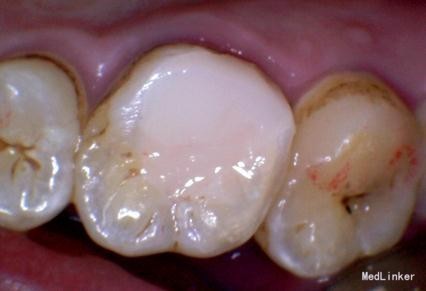

诊断:#26牙髓炎 治疗计划:#26根管治疗,后期纤维桩加固嵌体保护冠修复。局部麻醉下开髓,根管预备,消毒。(近中发现mb2)